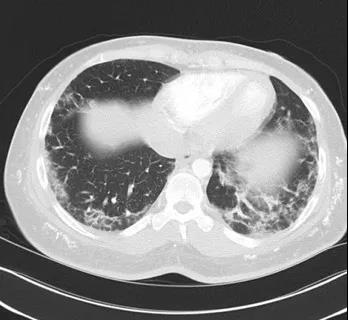

皮肌炎患者的胸部CT:肺间质病变